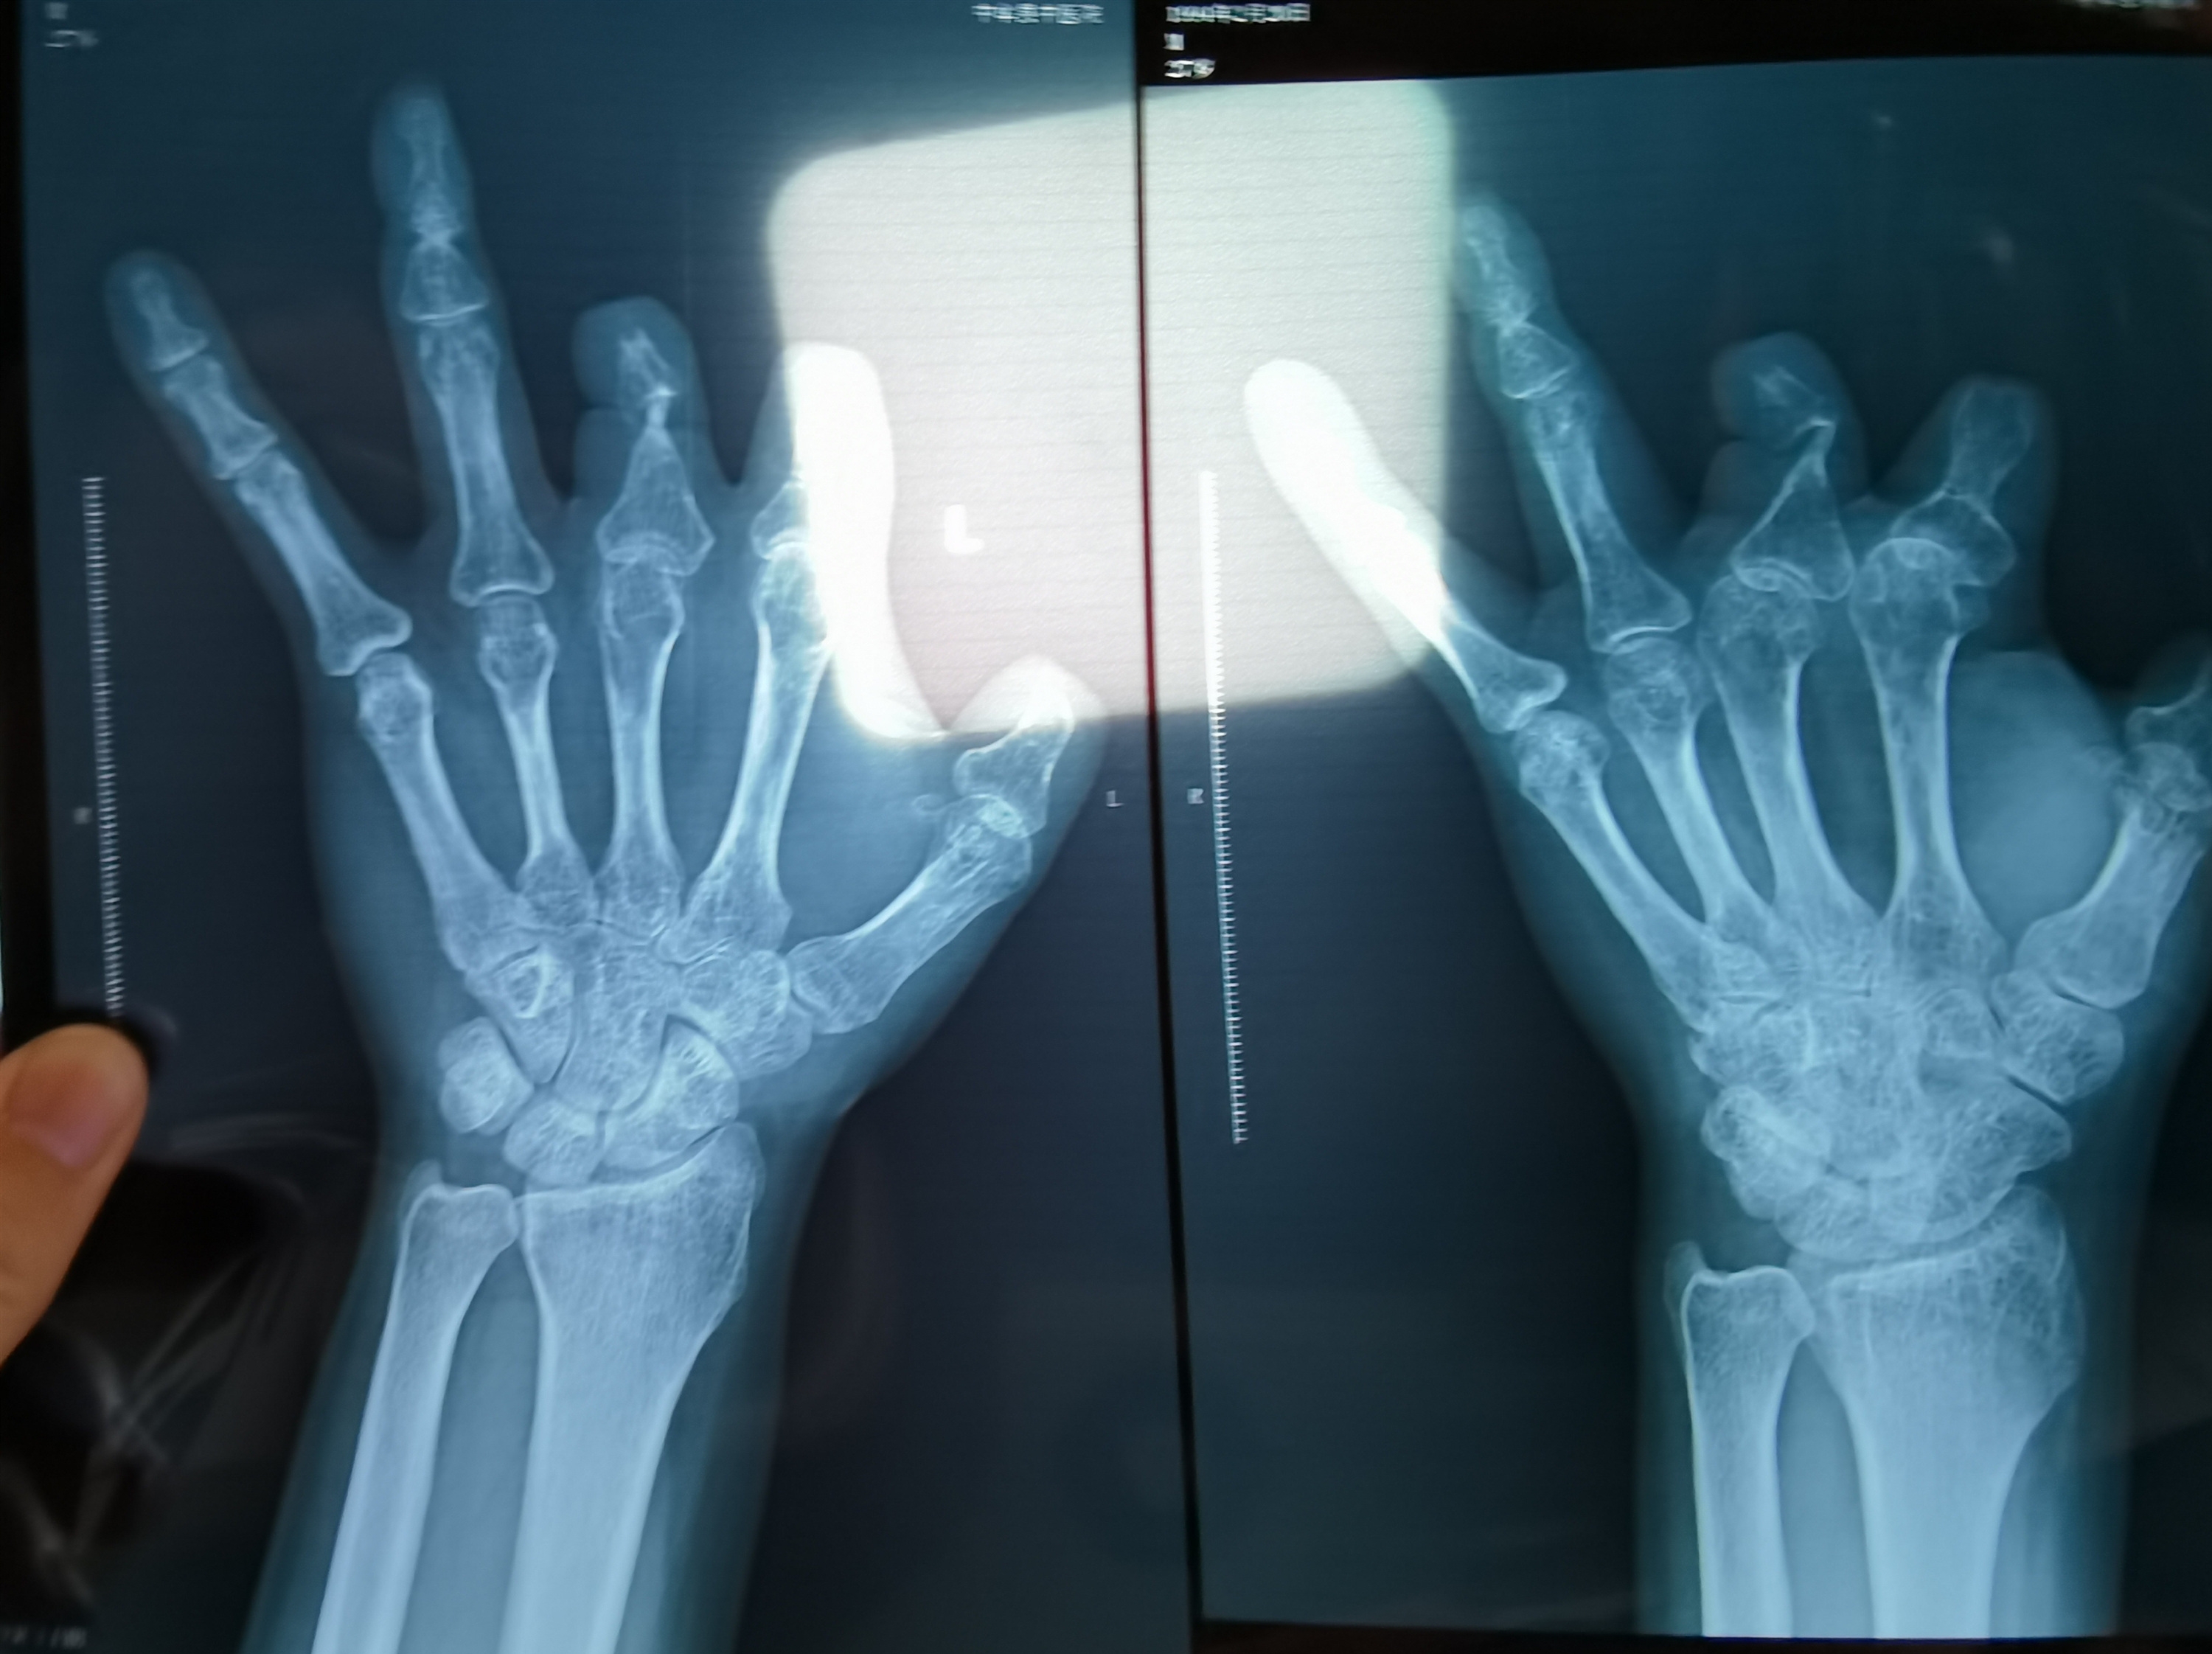

患者王海森左手拇指关节以上部位被电锯切断,收费单显示术中使用了微血管吻合装置,但X光片中未显示该器械。新京报记者 程亚龙 摄

该产品的代理商曾向新京报记者证实,微血管吻合装置为植入型医疗器材,患者拍摄X光片时会有显示。新京报记者获取了一位曾在郑大一附院接受手术、使用了该产品的患者的X光片,其手术部位可见一绿豆大小的光圈。

王海森称,他出院约1年后,有人曾找到他说,这个价格昂贵的进口器材,并没有在手术中使用。当时他没有相信,直到2021年12月,经人提醒,王海森在老家开封尉氏县人民医院拍摄了左手X光片,才确认手术部位的确没有微血管吻合装置。2021年12月底,王海森向郑州市公安局二七分局刑侦大队报案。

2021年12月,患者彭先生拍摄的左手X光片,未见收费单据中列出的微血管吻合装置。新京报记者 程亚龙 摄